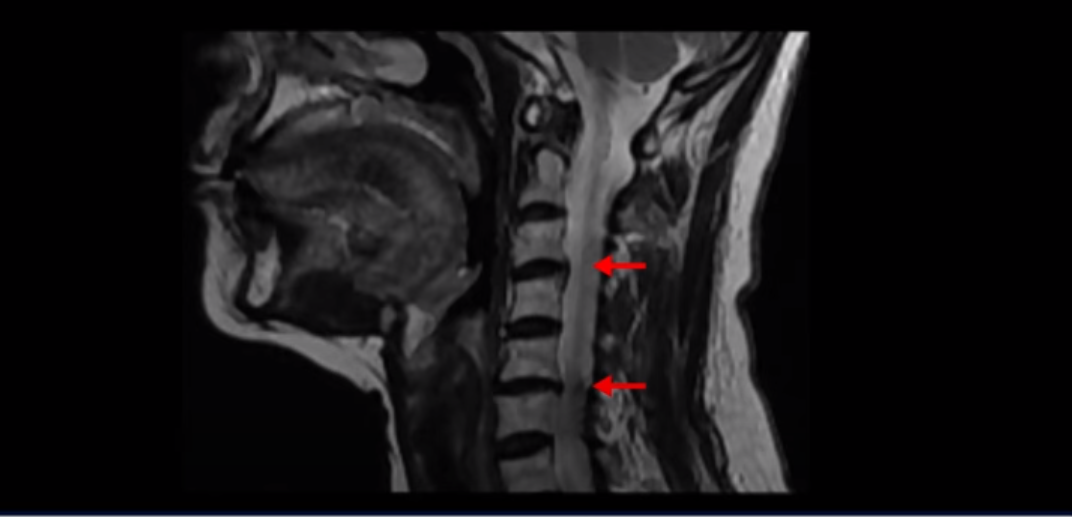

이 환자분은 원인을 알 수 없는 두통, 어지럼증, 메스꺼움, 눈 통증, 눈 침침함, 이명, 팔 통증 팔힘빠짐, 안면 감각 이상과 함께 극심한 목 통증과 어깨통증, 견갑골 통증을 3년 이상 겪으셨습니다. 이런 복합 증상들은 거북목으로 인해 목 근육, 특히 목 앞쪽 근육이 극심하게 뭉칠 때 나타나는 증상입니다. 이런 여러 가지 증상이 나타나는 이유는 거북목으로 인해 극심한 목 근육 뭉침, 특히 목 앞쪽 근육의 단축과 뭉침이 지속되면 목 근육 사이를 통과하는 목 주변의 혈관과 신경에 큰 영향을 미치기 때문입니다. 이 환자분은 고개를 숙이면서 하는 일을 오래하셨고, 그런 이유로 거북목으로 인한 목 앞쪽 근육 및 목 뒤쪽 근육 뭉침 모두 매우 심한 상태였습니다.

일반적으로 환자분들이 어지럽고 두통도 있고 하면 보통 이비인후과나 신경과에 많이들 가시는데, 목 문제 때문에 아픈 사람들은 당연히 이비인후과에서는 이상이 없다는 얘기를 듣고 또 신경과에서도 아무 이상이 없다고 듣거나 혹은 후두신경통을 진단받는 경우가 많습니다. 또 만성적으로 목과 어깨 근육이 뭉치면서 목 통증, 어깨통증이 있기 때문에 정형외과나 통증의학과, 한의원 등에 가면 근막통증증후군 같은 진단을 받는 경우도 많습니다. 게다가 이렇게 목이 아픈 환자분들은 척추병원에 가서 MRI를 찍어보면 이 환자분처럼 40세가 넘은 분들은 퇴행성 목디스크가 보이는 경우가 매우 많습니다.

이 환자분도 역시 이렇게 목디스크가 보이기 때문에 척추병원에서 목디스크 때문이라는 얘기를 듣고 신경 주사를 여러 번 맞게 되지만 목디스크 때문에 아픈 게 아니기 때문에 목디스크를 계속 치료해봐야 좋아지지 않는 겁니다.